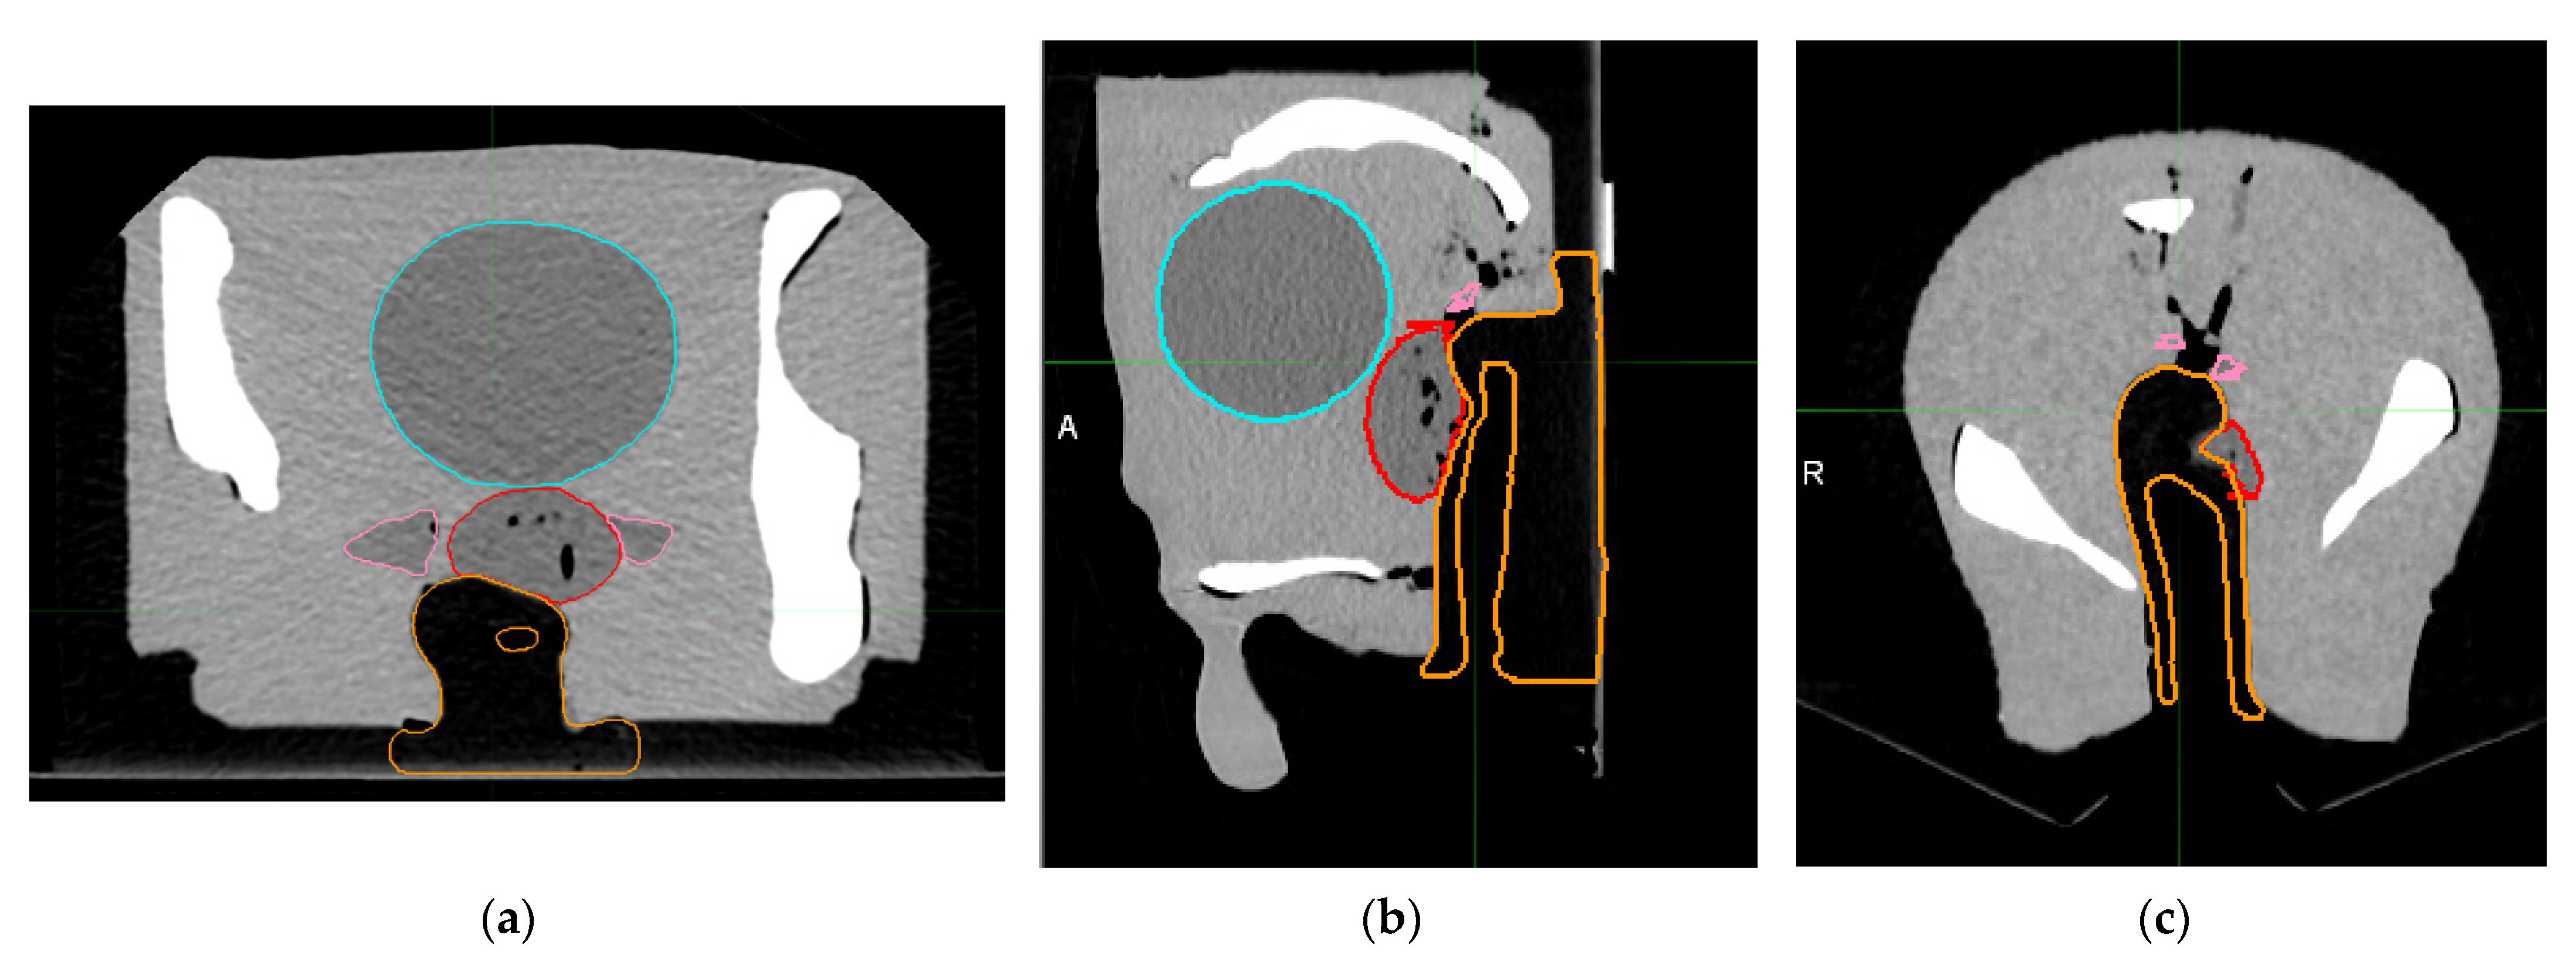

2.4. Dose Distributions

3. Results

3.3. Dose Distributions